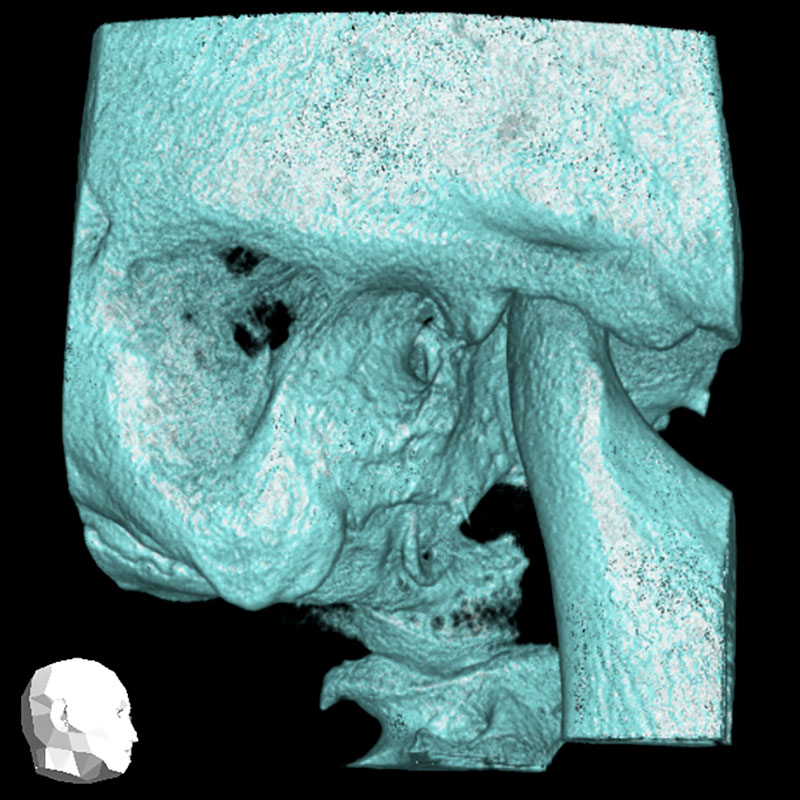

Ihre Praxis für die digitale Volumentomographie (DVT)